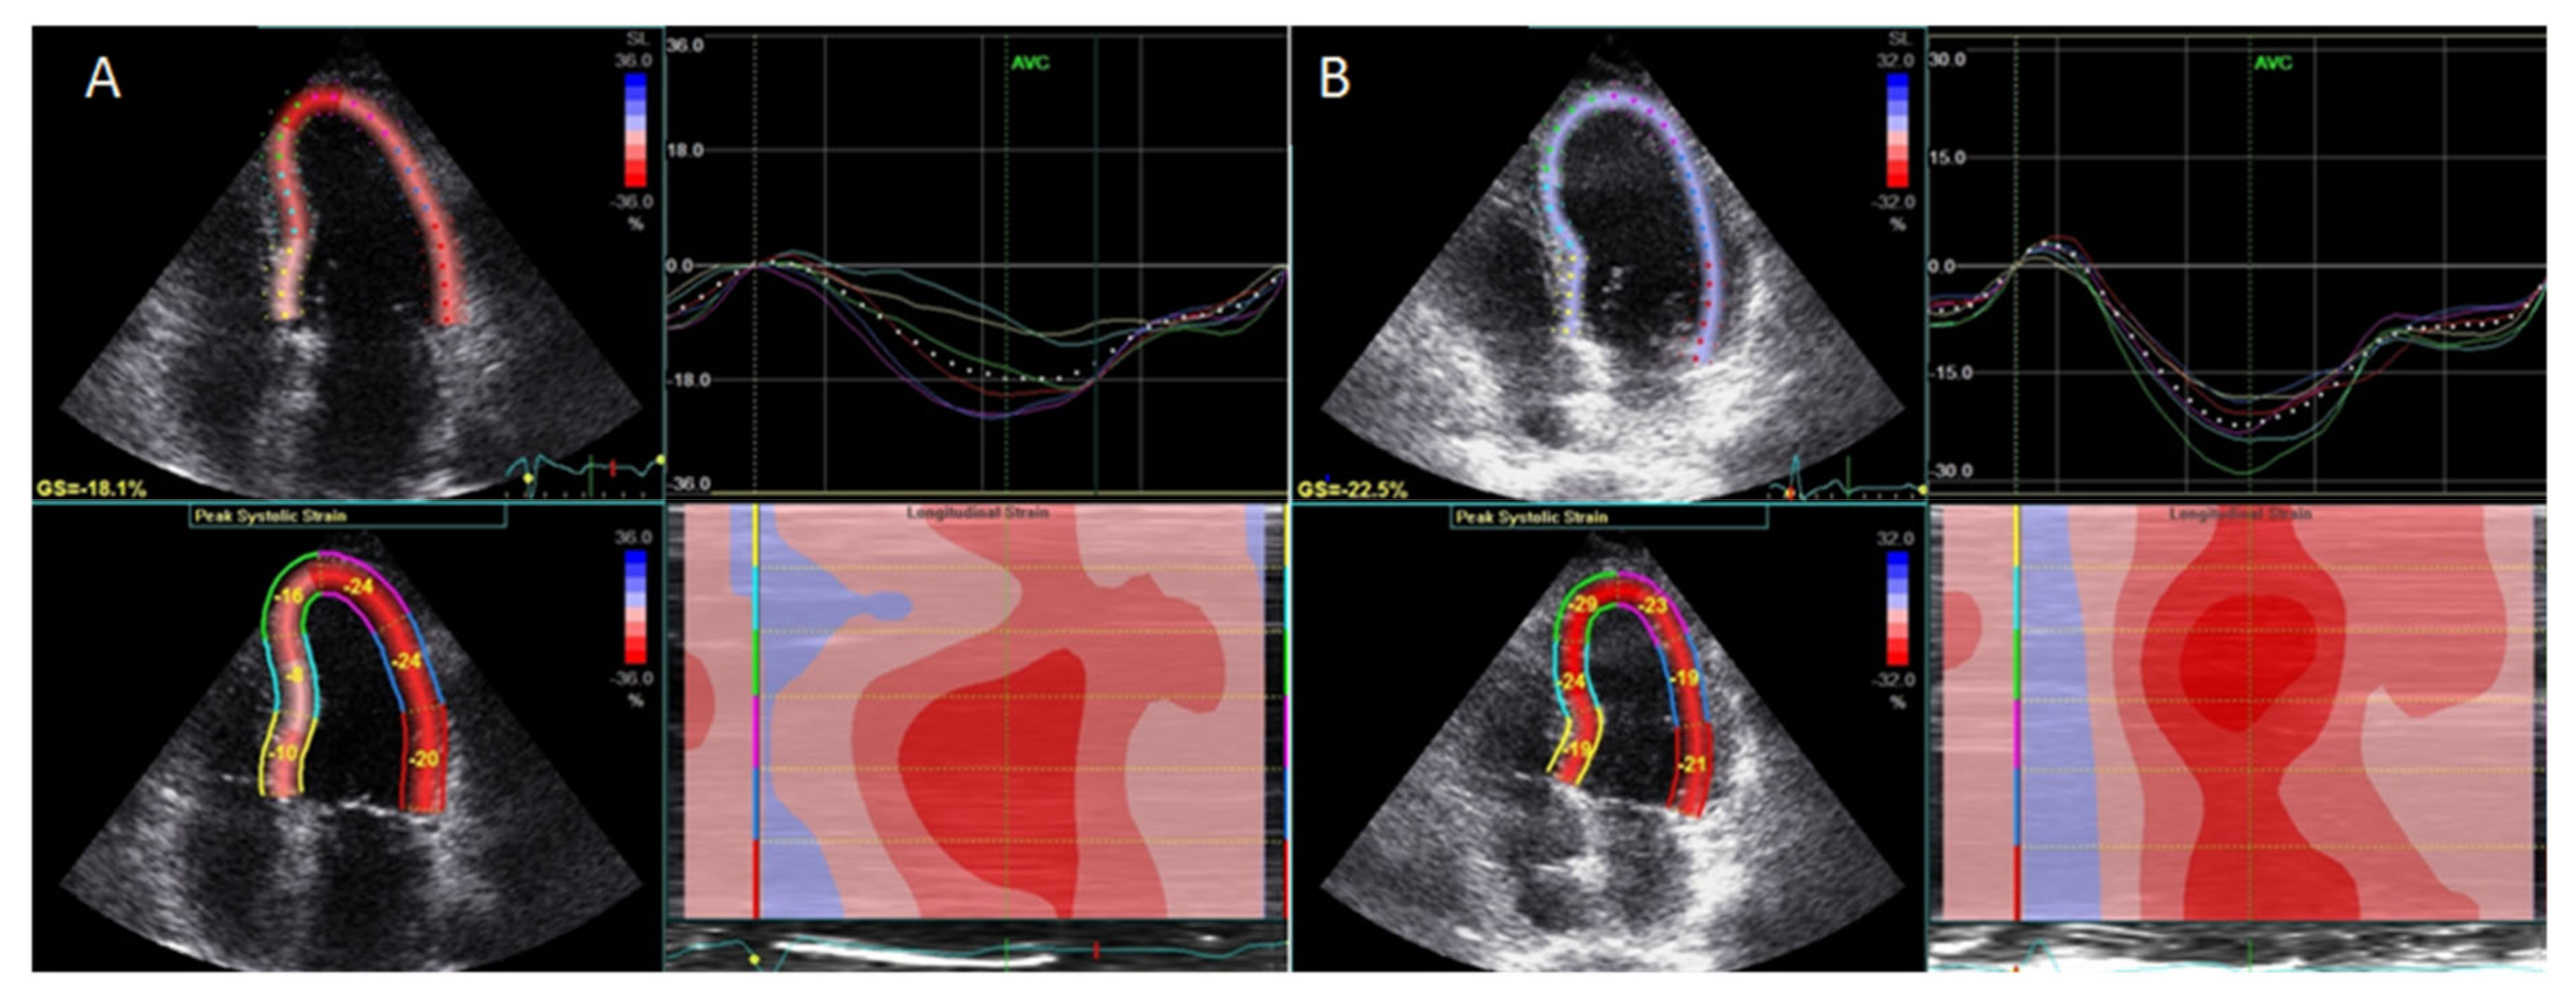

- Ikonomidis, I.; Papadavid, E.; Makavos, G.; Andreadou, I.; Varoudi, M.; Gravanis, K.; Theodoropoulos, K.; Pavlidis, G.; Triantafyllidi, H.; Moutsatsou, P.; et al. Lowering interleukin-12 activity improves myocardial and vascular function compared with tumor necrosis factor-a antagonism or cyclosporine in psoriasis. Circ. Cardiovasc. Imaging 2017, 10, e006283. [Google Scholar] [CrossRef] [PubMed]

- Makavos, G.; Ikonomidis, I.; Andreadou, I.; Varoudi, M.; Kapniari, I.; Loukeri, E.; Theodoropoulos, K.; Pavlidis, G.; Triantafyllidi, H.; Thymis, J.; et al. Effects of interleukin 17a inhibition on myocardial deformation and vascular function in psoriasis. Can. J. Cardiol. 2020, 36, 100–111. [Google Scholar] [CrossRef] [PubMed]

| Subclinical LV dysfunction Subclinical RV dysfunction | Impaired GLS | GLS >−20% |